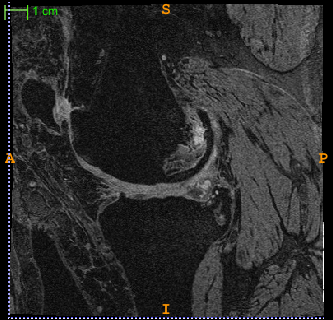

The quantitative analysis of knee cartilage is advantageous for the study of cartilage morphology and physiology. In particular, it is an important prerequisite for the clinical assessment and surgical planning of the cartilage diseases, such as knee osteoarthritis which is characterized as the cartilage deterioration and a prevalent cause of disability among elderly population. As the leading imaging modality used for articular cartilage quantification [1], magnetic resonance (MR) imaging provides direct and noninvasive visualization of the whole knee joint including the soft cartilage tissues (Fig. 1c). However, automatic segmentation of the cartilage tissues from MR images, which is required for accurate and reproducible quantitative cartilage measures, still remains an open problem because of the inhomogeneity, small size, low tissue contrast, and shape irregularity of the cartilage.

Figure 1: (a) The bone segmentation framework. (b) 3D anatomy of knee joint. (c) Example of a 2D MR slice [6]. (d) The semantic context forests diagram.